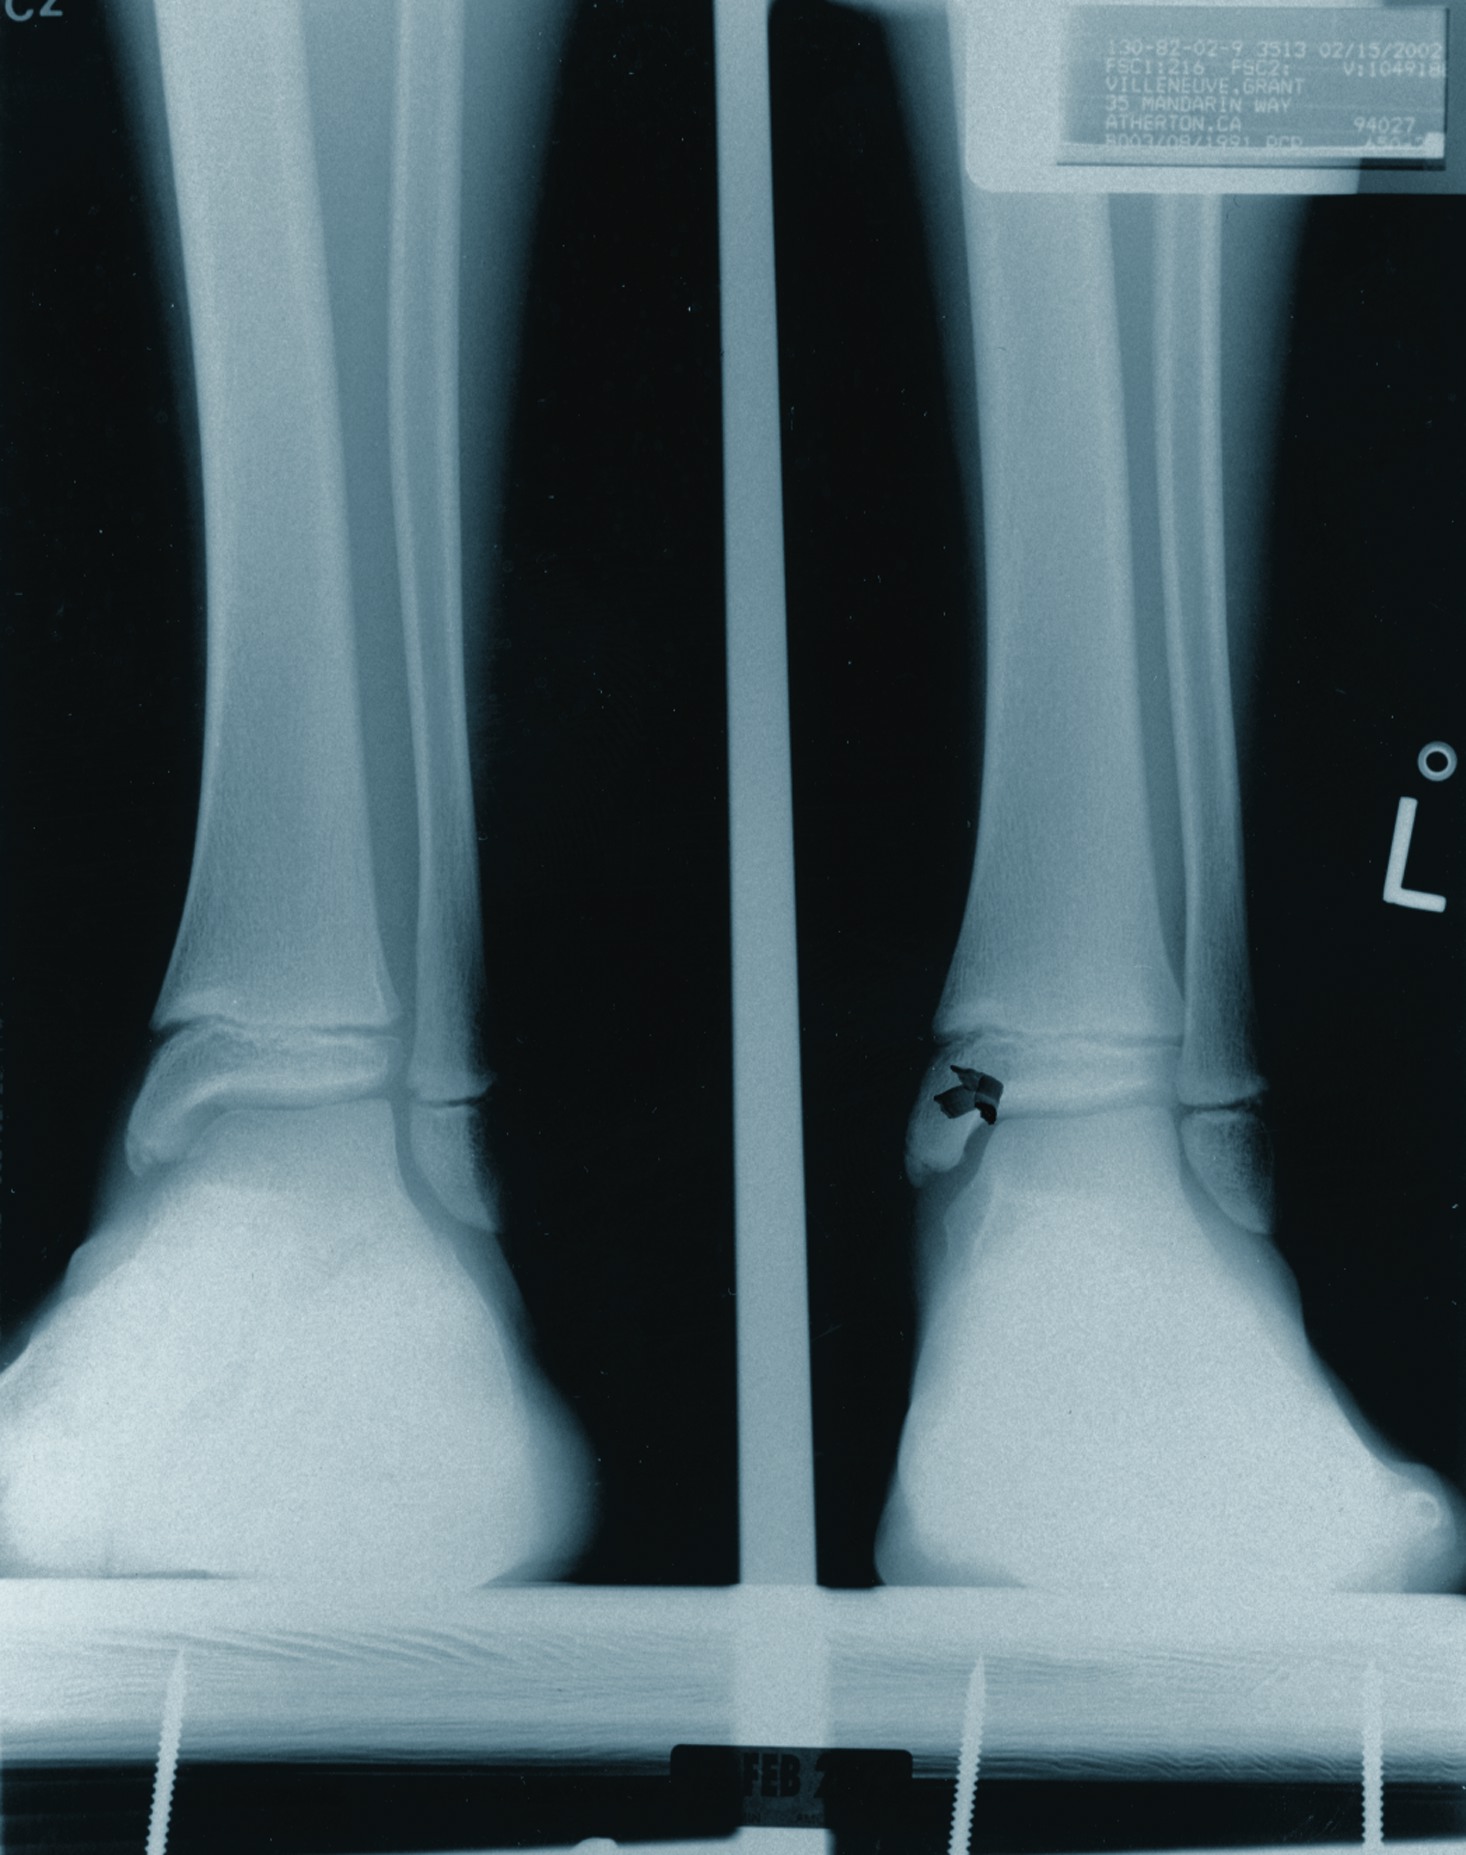

Following heel strike, the subtalar joint pronates, the calcaneus everts and the talus plantarflexes and adducts. Excessive movement in the direction of pronation results in the foot losing its ability to resupinate with ultimate collapse of the medial arch. The purpose of arthroereisis devices is to limit excess subtalar joint motion in the direction of pronation and still allow the joint to supinate. Chambers first described the concept of using an implant to limit subtalar joint motion in 1946. He used a bone graft to elevate the floor of the sinus tarsi in order to prevent subtalar joint eversion.1 Many have followed with various arthroereisis implant devices. Smith popularized the procedure in the podiatric profession in the early 1970s with the development of the STA-Peg.2 This polyethylene implant sat in the floor of the sinus tarsi and allowed the talus to move forward but at an oblique angle to the joint surface. This limited STJ motion by its “axis-altering” properties. Although the implant was originally cemented into the calcaneus to prevent loosening, this technique was discontinued due to potential complications associated with the use of bone cement although no adverse consequences were noted. Subsequently, a number of implants have emerged over the years. The majority of these subtalar implants occupy the soft tissue content of the sinus tarsi in order to limit the anterior movement of the talus on the calcaneus. Green, et. al., offered a comprehensive review of this procedure and other devices earlier this year.3 Maxwell and Brancheau developed the MBA implant nearly 15 years ago as an alternative arthroereisis device for people with flexible flatfoot deformity.4,5 This is a “free floating” device in the sinus tarsi that “blocks” anterior talar movement. The device’s ease of insertion, lack of complications and overall benefit has made this one of the most commonly used implants in foot surgery. Over the years, multiple studies have documented the success of the arthroereisis procedure in children and, more recently, in adults.4-7 Needleman recently published a retrospective study of the MBA implant in the adult flatfoot and reported a 78 percent satisfaction rate.6 The most common complication in this study was sinus tarsi pain, which occurred in 13 of 28 feet (46 percent). This complication required implant removal in 11 patients but none of these implants were removed earlier than eight months postoperatively. Interestingly, radiographic parameters after implant removal remained unchanged with no loss of correction. Perhaps the most commonly reported complication of arthroereisis procedures is sinus tarsi pain, which occurs in 5 to 10 percent of patients.8 This often resolves with rest, casting, orthotics, cortisone injection or a combination thereof. The prevailing thinking is this pain is both a reactive synovitis and bone contusion from the significant compressive forces generated by and upon the implant. Poor implant sizing, implantation and loosening may play a role as well. These findings appear to be much more common in the adult than in the juvenile patient. Recently, Kinetikos Medical has released the resorbable bioBlock® arthroereisis implant. This is a near duplicate of the MBA implant in terms of shape, design and the method of implantation. It is made of poly-L-lactic acid (PLLA) and is therefore radiolucent. Once one has inserted the implant, the clinician can obtain an X-ray with the driver in place in order to assess the final position of the implant. Its resorption characteristics are still unknown. According to the company, an 8 mm implant placed in a saline bath to simulate the body’s environment demonstrated no loss of mechanical strength at eight months. However, much is known about PLLA and other bioresorbable materials.

Various authors have reported a wide range of applications for bioabsorbable implants in the literature, including the use of these modalities in osteotomies, fractures and arthrodeses. However, the surgeon must remember that in comparison to traditional metal implants, bioabsorbables possess inferior mechanical properties.18 Therefore, surgeons should reserve the use of these implants for instances when minimal load and stress will be applied, when healing will occur before the implant loses significant strength, and when surgeons would remove the implant under normal circumstances.9 Medial malleolar fractures and syndesmotic injuries are currently the most accepted applications for absorbable fixation. Bucholz, et. al., randomized 155 patients with displaced medial malleolar fractures.19 They managed one group with 4.0 mm stainless steel fixation while managing the other group with 4.0 mm PLA screw fixation. There was no significant difference between the groups in terms of fracture healing, postoperative complications or functional results. In addition, at an average follow-up of 37 months, no inflammatory reactions occurred in the PLA group. Hovis, et. al., followed 23 patients with PLLA screw fixation of syndesmotic injuries for an average of 34 months.18 All patients returned to pre-injury levels of activity within the time of follow-up. There were no reactions to the absorbable material and no secondary procedures were required. The authors conclude that PLLA screws are ideal for fixation of these injuries because compression is not required in syndesmotic repairs. Thordarson, et. al., compared bioabsorbable fixation to stainless steel screw fixation of syndesmotic injuries in pronation-external rotation ankle fractures.20 In a randomized study, the authors utilized fixation with a 4.5 mm PLA screw for 17 patients and employed a 4.5 mm stainless steel screw for 15 patients. After 11 months, all fractures healed uneventfully. In addition, there were no wound complications, no radiographic osteolytic changes and no inflammatory reactions in the PLA group. The Lisfranc injury represents another clinical scenario in which approximation has more vital importance than compression. These injuries also typically require hardware removal after standard open reduction internal fixation (ORIF) with metal implants. Accordingly, Lisfranc injuries seem extremely conducive to bioabsorbable fixation. Thordarson and Hurvitz used PLA screws in 14 patients with Lisfranc fractures/dislocations.21 There was no loss of reduction after an average 20-month follow-up. There were also no reports of soft tissue or bone reaction to the implants. Within a 10-year period, Rokkanen, et. al., performed a total of 2,500 orthopedic procedures using bioabsorbable materials.22 They reported fixation failure in 3.7 percent of the patients with PGA implant cases and encountered non-infectious inflammatory reactions in 2.3 percent of patients with PGA implants. The reaction appeared postoperatively at two to three months. However, no reactions occurred with the use of PLA implants. Bioabsorbable implant use in pediatric patients is still under debate. Researchers published an experimental study on the effect of PDS implants placed across the growth plate of rabbits in 1989.23 A transphyseal 2.0 mm PDS implant showed no permanent growth disturbance and no histomorphometric change in comparison to a control. Böstman, et. al., published a study of PGA pins in treating 71 fractures in skeletally immature patients. According to the study, 87 percent of patients experienced anatomic healing until union.17 Still, the authors recommended long-term clinical studies before widespread use becomes commonplace for pediatric patients. However, keep in mind that these studies dealt with implanting devices into bone as opposed to soft tissues. There are two publications on results with resorbable sinus tarsi implants. Giannini initially reported on a four-year follow-up of an absorbable sinus tarsi implant.24 The study evaluated the Stryker Howmedica PLLA bioabsorbable subtalar implant, which is not available in the United States. The authors treated 21 children with flexible flatfoot. The children ranged from 8 to 15 years of age. The researchers performed Achilles tendon lengthening in six feet and performed a modified Kidner in 12 feet. In a four-year follow-up study, the authors reported that only 5 percent of the patients had pain as opposed to 81 percent of patients who had preoperative pain.24 Whether this pain was related to the implant is not clear. No implants had to be removed. The authors of the study obtained sequential MRIs from three months to five years postoperatively. There was no sinus formation or osseous changes. Changes in implant resorption began to show at six months and fragmentation was noted at one year. However, the overall structure appeared to remain intact. A loss of structural integrity with fragmentation occurred by 18 months. The authors of the study saw complete resorption at four years postoperatively.24 The only reported complication was impingement of implant fragments against the shoe in two patients at one and two years postoperatively. Both resolved with the complete resporption of the material. Keep in mind that the design of the Stryker Howmedica PLLA bioabsorbable subtalar implant is considerably different than the bioBlock implant, which is available in the U.S. Most recently, Giannini, et. al., published a study involving 12 patients (14 feet). For these patients, they resected a tarsal coalition in the middle facet of the subtalar joint and subsequently implanted the Stryker absorbable sinus tarsi implant to correct the symptomatic flatfoot.25 All patients presented with hindfoot pain preoperatively and only 5 percent had this pain postoperatively. The results showed eight excellent, three good and three fair results subjectively with AOFAS scores improving in all 14 feet based on pain reduction, hindfoot alignment and ROM.25 There was no discussion of the implant other than its value in correcting a pronated foot.

To answer the question of whether bioresorbable implants work, the answer appears to be yes. Although there are only two published studies on bioresorbable implants in juveniles, both of which are favorable, the design characteristics of the bioBlock implant are nearly identical to those of the well documented MBA implant. Accordingly, one would expect similar results. As to the question of whether the bioBlock implant is better, the answer is unclear at this time. The company states that one potential advantage is for parents who do not want a permanent metallic implant in their child’s foot. Although this is true, this concern is only raised in a small number of patients. As noted earlier, subtalar joint pain is the most common complication of arthroereisis devices. If we assume the implant was the correct size and was properly inserted, will resorbable implants lower this complication rate? Sinus tarsi pain is, in part, a reactive inflammatory response secondary to the compressive forces between the talus, calcaneus and the interposed implant device. As the implant begins to resorb and lose its structural integrity, these forces should diminish with subsequent reduction of clinical symptoms. Needleman noted that, in most patients, the sinus tarsi pain began shortly after weightbearing and ultimately required removal in 9 of 12 feet between seven and 12 months postoperatively.6 Therefore, if the implant does not lose its structural integrity until 18 months postoperatively in children as reported by Giannini, the implant will probably not resorb quickly enough to prevent its removal secondary to sinus tarsi pain.24 Resorption times for bioabsorbable subtalar joint implants are unknown in adults but probably exceed that of children due to decreased vascularity. Kinetikos Medical recommends maximum patient body weights for each diameter implant. For an 8 mm implant, the maximum body weight would be 150 lbs. For a 9 mm implant, it would be 180 lbs. For a 10 mm implant, it would be 220 lbs. For an 11 mm implant, it would be 250 lbs. For a 12 mm implant, it would be 250 lbs. Exceeding these limits may cause the implant to deform. It is unlikely this alteration of shape will result in loss of correction but it may reduce compressive forces within the sinus tarsi. Additionally, the implant, due to its viscoelastic properties, does have the capacity to deform under pressure. These factors may lessen the incidence of sinus tarsi pain. Loosening is rarely a problem with most sinus tarsi implants that are properly inserted. Soft tissue ingrowth helps to stabilize these implants, which are not inserted into bone. Scar tissue encompasses the implant and occupies the spaces between the threads and central cannula. With resorbable implants, as the structure loses its integrity, this stability will be lost and implant loosening may occur. If removal of the implant or its fragments is required, this could prove difficult as the material is radiolucent. Although the incidence of adverse reactions to PLLA is less than 1 percent, foreign body reactions are still possible, especially when the implant fragments and shards are dispersed into the soft tissues. The final and perhaps most important question to consider is the long-term efficacy of resorbable sinus tarsi implants for the correction of flatfoot deformity. Needleman demonstrated no significant change in radiographic parameters after implant removal at an average follow-up time of nearly four years.6 All patients had either a heel cord lengthening and most had adjunctive forefoot procedures so it is difficult to isolate the effect of implant removal. However, these findings are consistent with other reports in the literature (among both adults and children) of persistent correction despite implant removal or resorption. An “arthrofibrosis” of the subtalar joint appears to develop and this may ultimately limit motion in the implant’s absence.